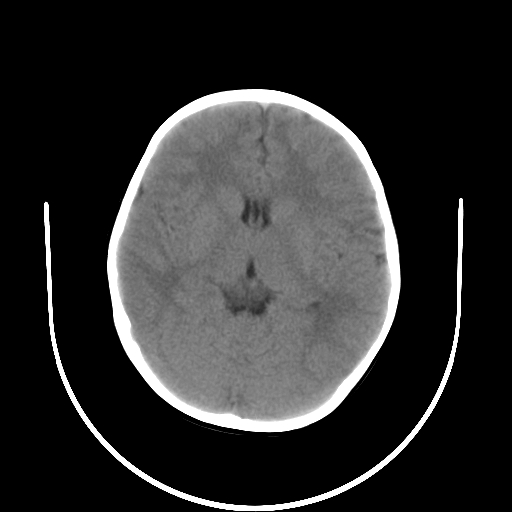

以下是引用拾荒者在2009-10-17 18:38:00的发言:[br]鼻面部皮下积气,右侧睑缘及眼球壁高密度异物影,左侧眼球壁晶状体内侧缘处是圆形低密度影。低密度异物?应提请眼科医生注意。